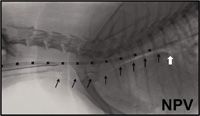

The use of computed tomography (CT), though not readily available at every institution, is becoming a more widespread modality for use in the small animal patient. Computed tomography affords a rapid evaluation of skeletal images with a small slice thickness that can be as small as 0.625.